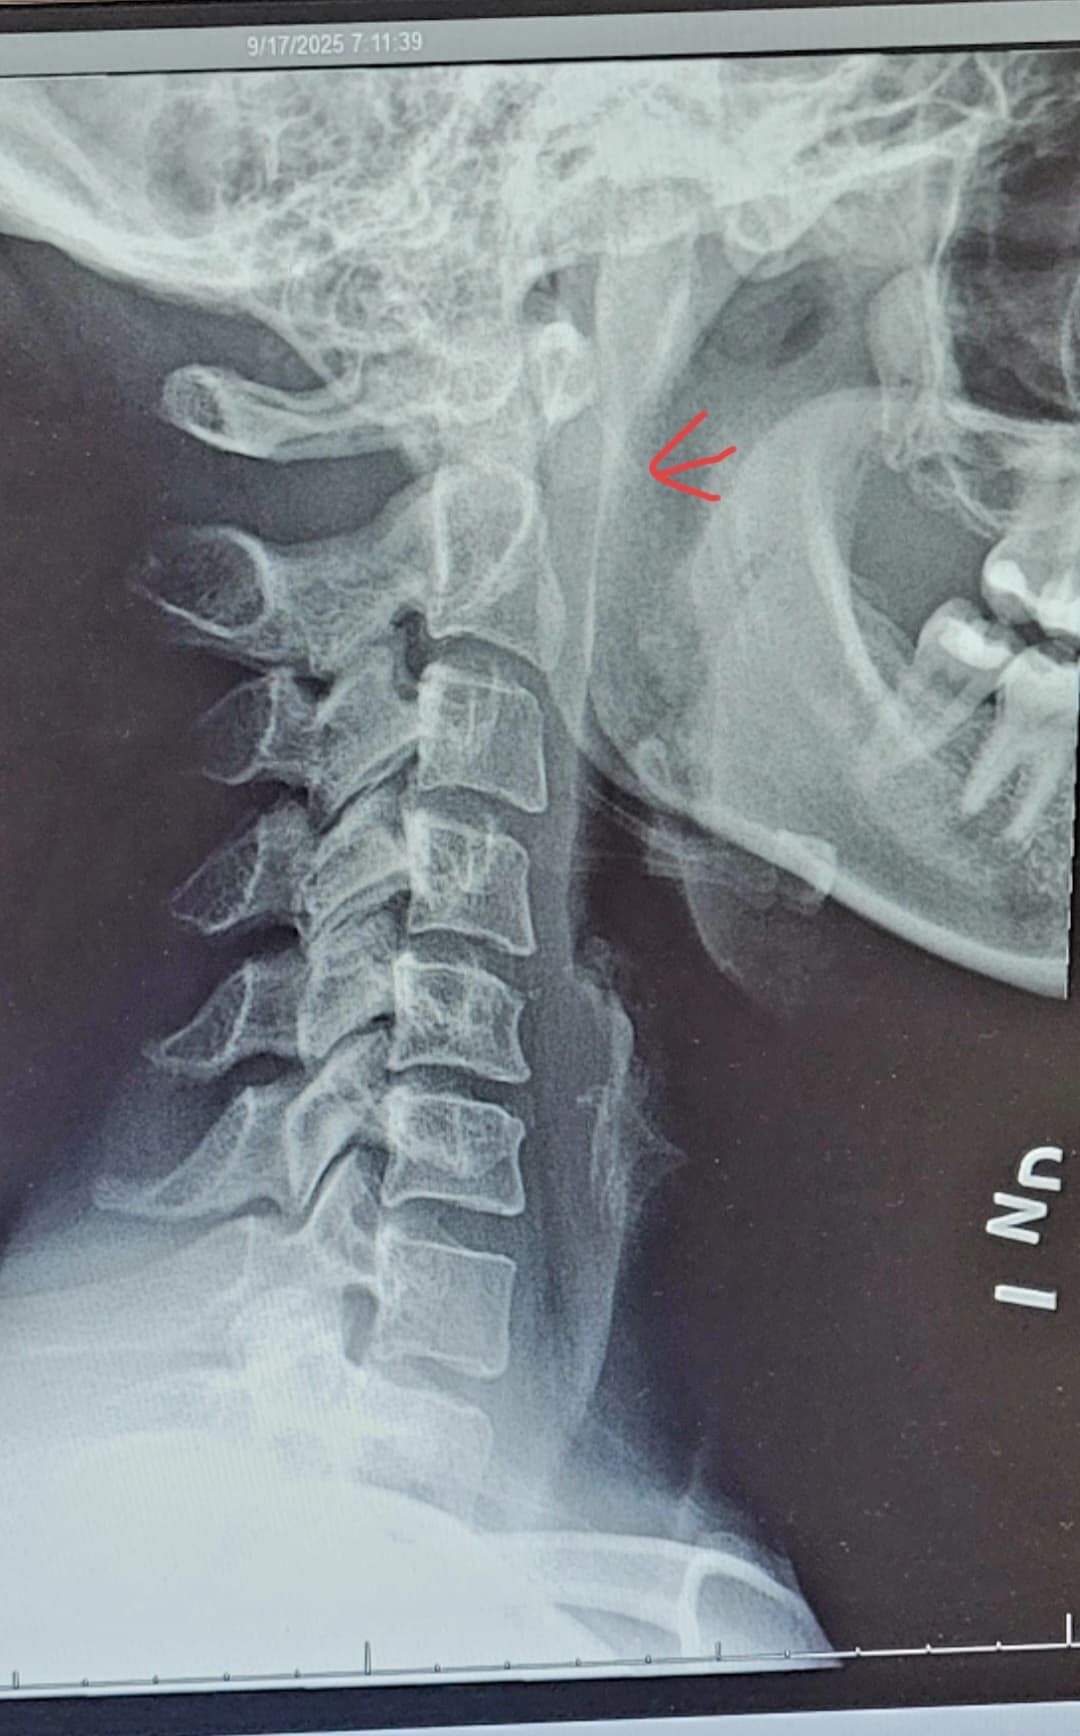

I am 31F, Lyme disease at 22, unilateral tinnitus in my right ear since 23, with various joint/ muscle pains since the onset of Lyme disease. MRI was performed to evaluate possible acoustic neuroma, negative finding.

Fast forward to this past month, I reviewed with my PCP that my right shoulder has been increasing in pain, especially after a day of working. I get a burning sensation in my neck/ occipital region which causes headaches and overall malice. I saw a orthopedist whom took x-rays and found that I have a straight neck.

When I was looking at my x-ray and researching straight neck I came across a radiology post on Reddit in which someone had straight neck along with calcified stylohyoid ligaments. I keep looking at my x-ray and honestly I can’t tell if mine is calcified or not. Neck x-ray is from this past week and dental pan is from 2024.

All my issues are on my right side, the grinding in my shoulder/ scapula region, the tinnitus in my ear (constant high pitch not pulsatile), the popping of my TMJ, all on my right side.

Lastly I have a MRI scheduled in October: MRI spine cervical WO contrast, and MRI shoulder right WO contrast.